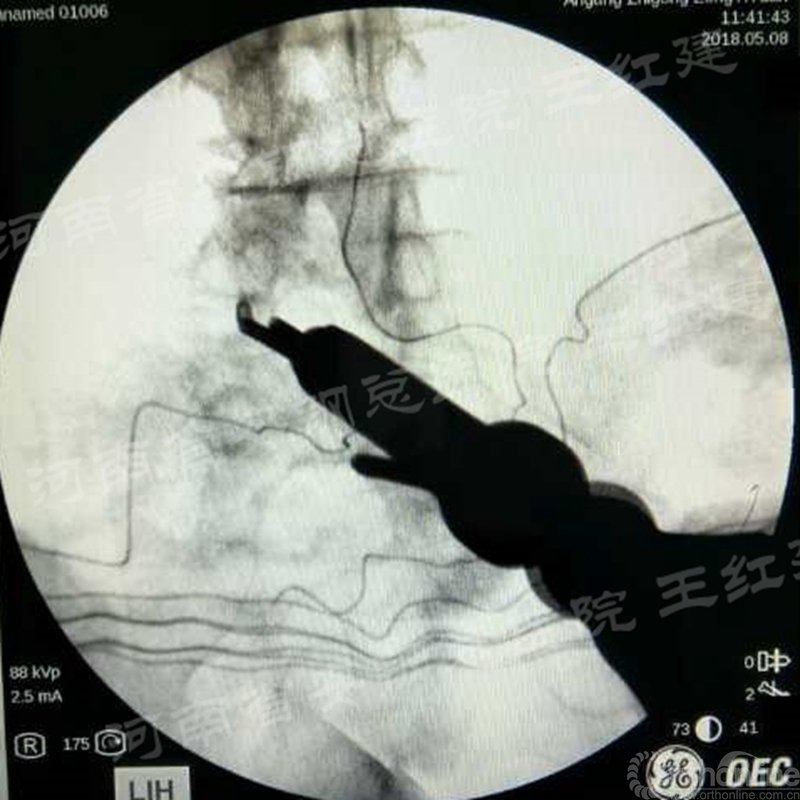

四、经皮螺钉技术固定

在固定的步骤可以先期进行经皮螺钉置入,再进行融合器的置入,进而实现充分固定。

椎弓根植入加压固定

单边椎弓根植入加压固定

双侧椎弓根植入加压固定

手术步骤:先期经皮螺钉置入、再进行融合器的置入